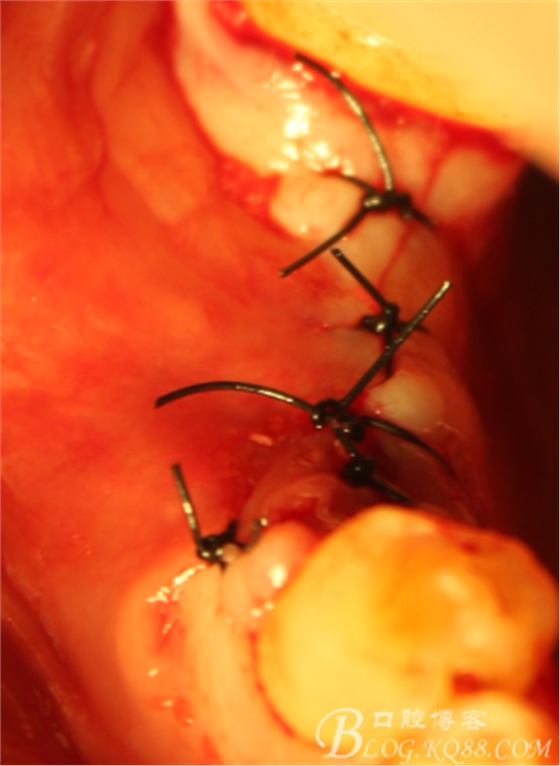

C6頰側(cè)填入自體骨,嚴(yán)密縫合關(guān)閉創(chuàng)口

三維檢查種植體位置,方向,平行度

上愈合基臺,間斷縫合關(guān)閉創(chuàng)口,頰側(cè)牙齦部分恢復(fù)形態(tài)